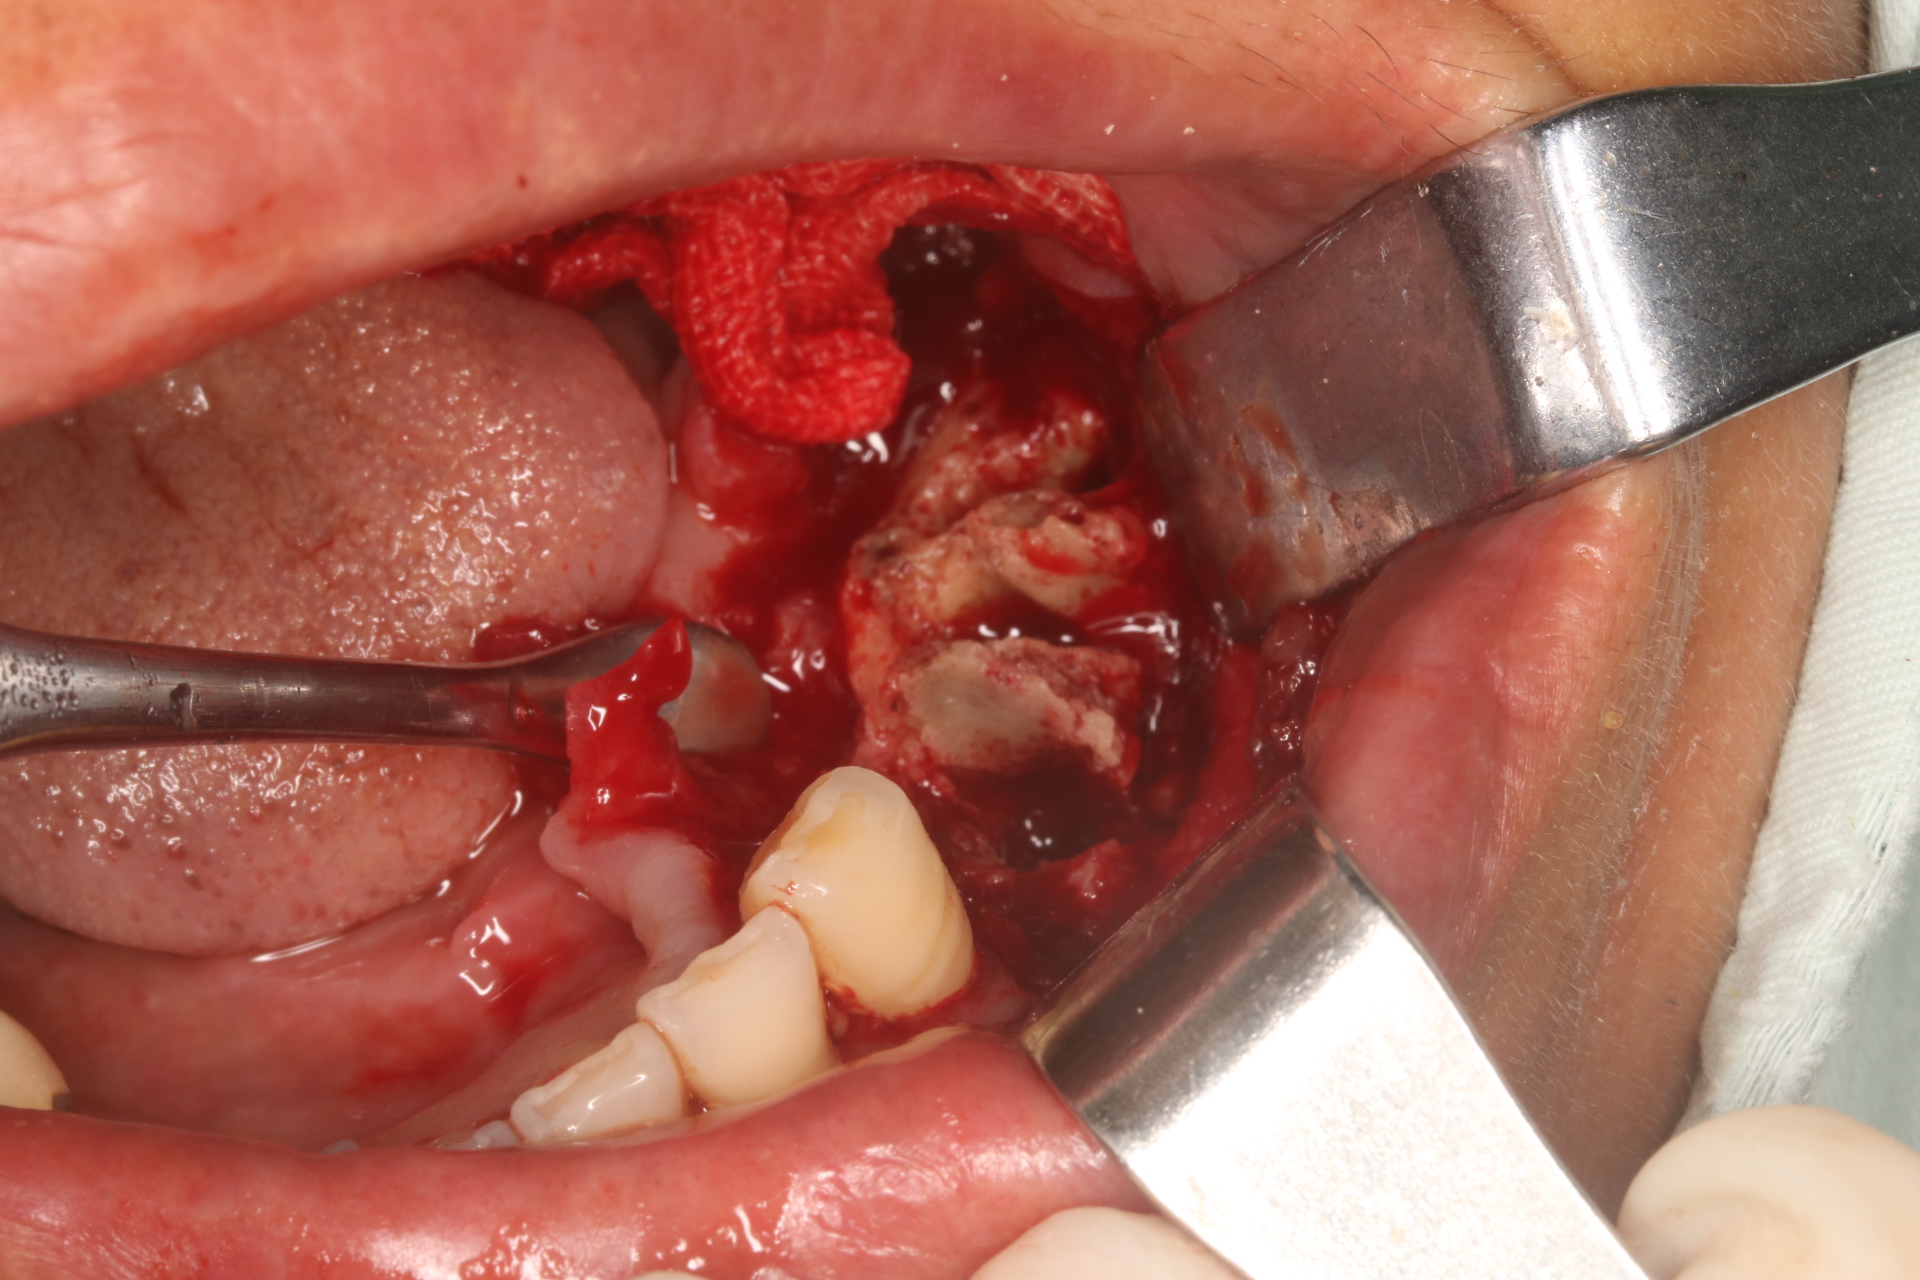

(患者应用双膦酸盐类药物导致颌骨坏死暴露。图片由作者提供)

随着更多的临床病例表现和和更深入的科学研究证实,越来越多的医生相信,骨质疏松症患者牙齿及口腔种植体周围的感染性炎症是MRONJ发生的重要局部因素。一方面,对接受骨改良药物治疗的骨质疏松患者进行牙槽外科手术,将会促进MRONJ的发生;另一方面,颌骨因其解剖结构、生理功能及口腔微生物环境等因素更易发生MRONJ。由于MRONJ发病机制尚无定论,影响的高危因素又多,治疗难度大,并可严重影响患者生活质量,目前尚无可靠方法来预测骨质疏松症治疗药物相关性颌骨坏死发生。因此,许多口腔科医生因顾虑MRONJ风险而不愿对此类患者进行治疗[3]。